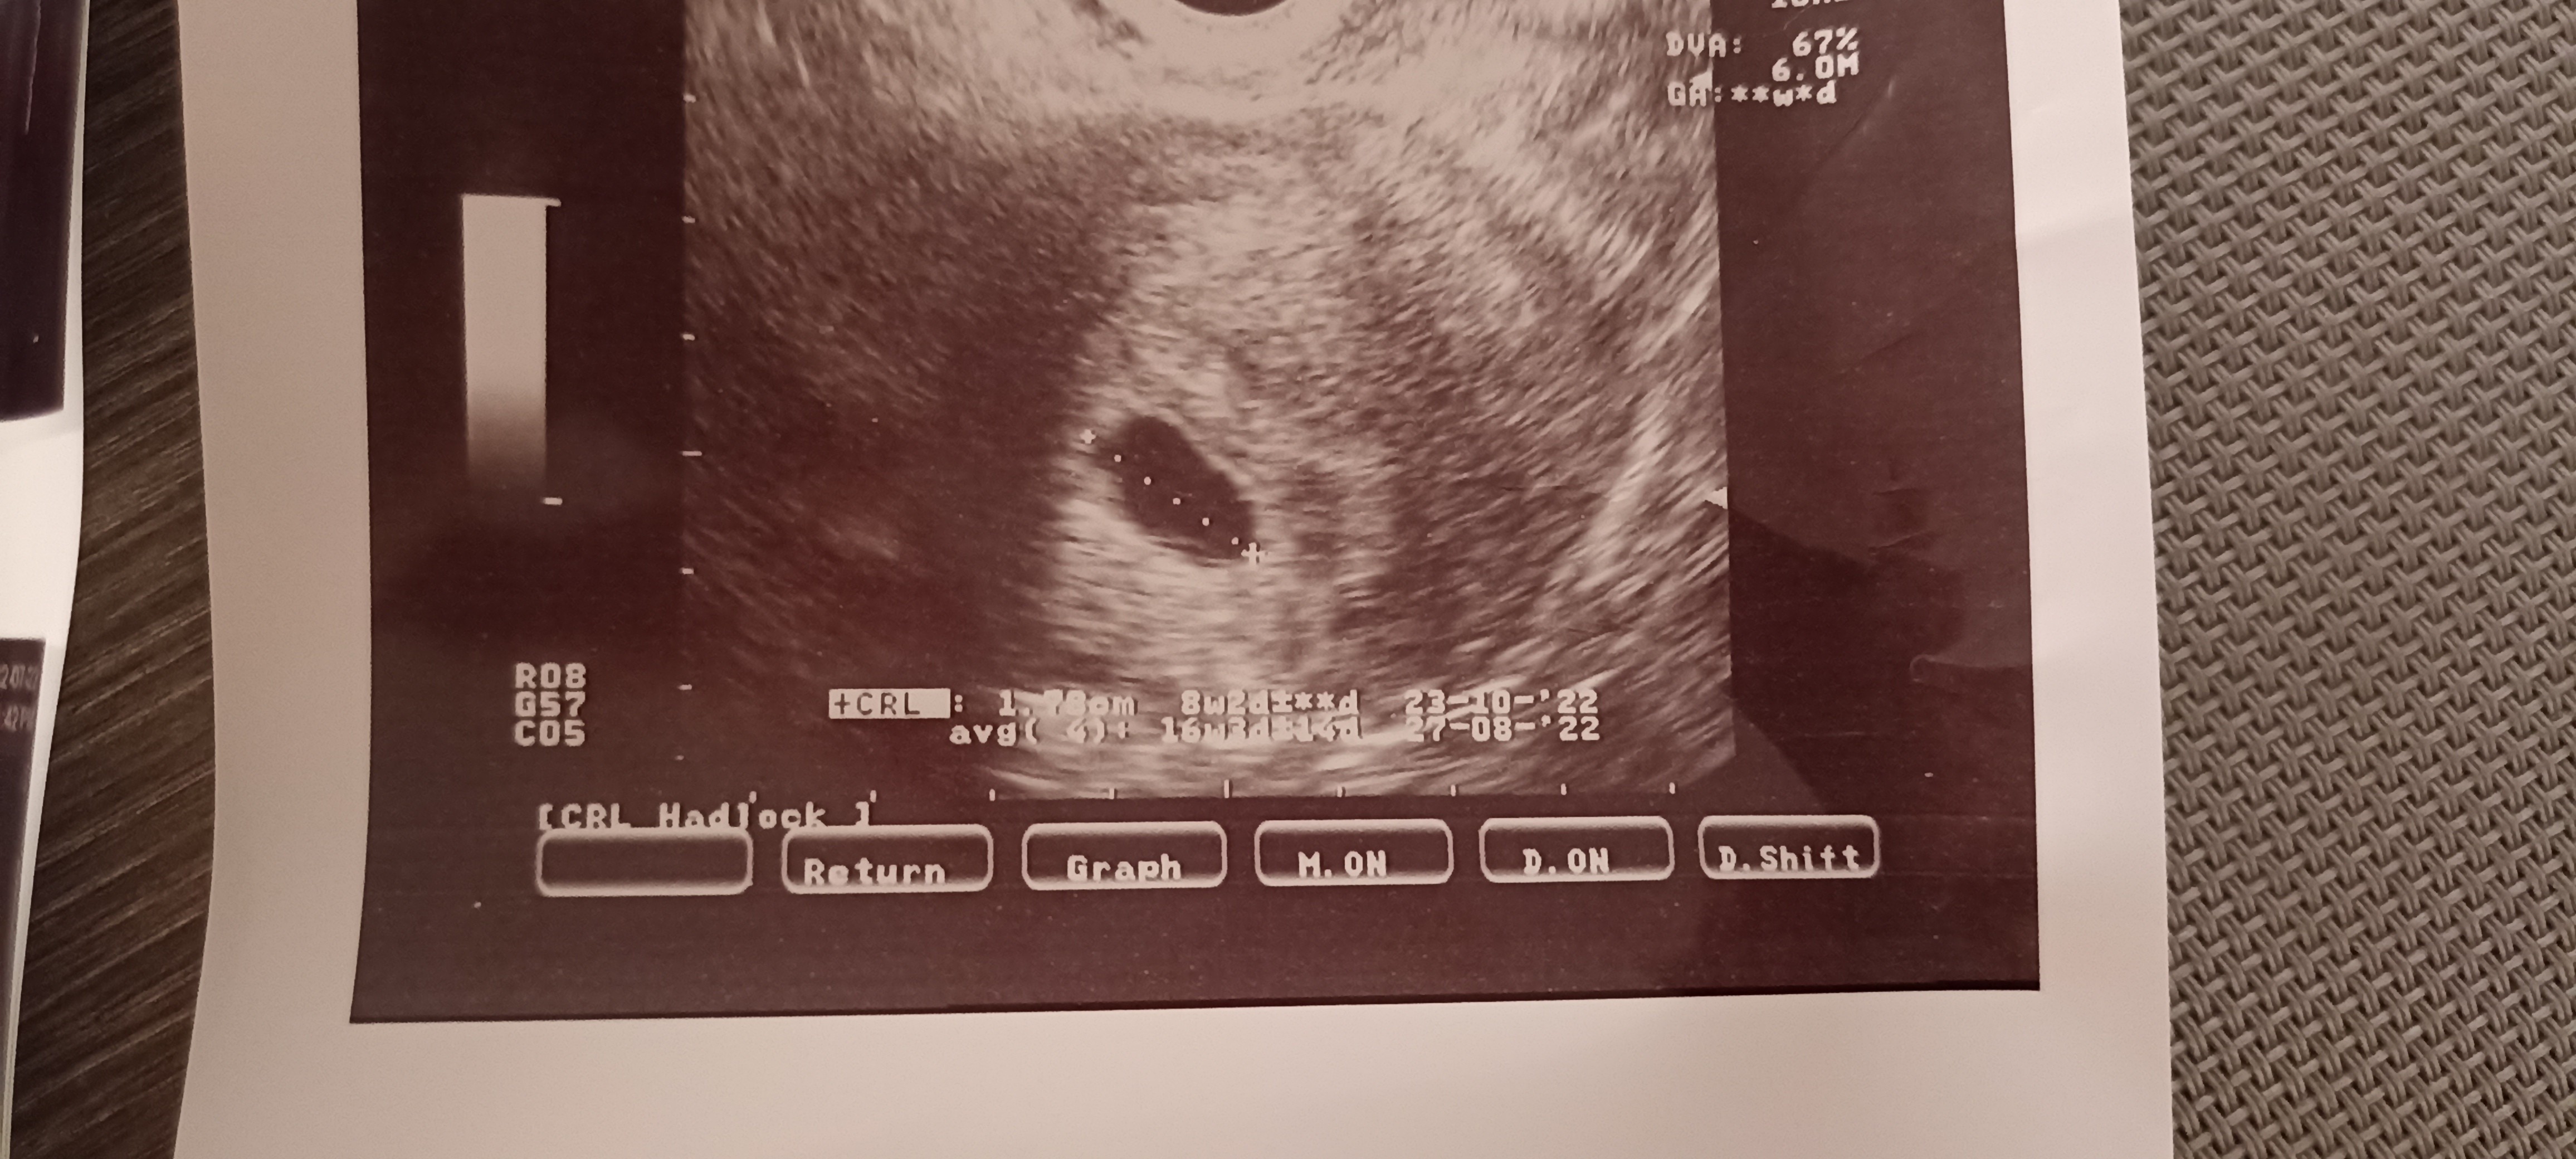

Ostatnia miesiączka 30 maj. Cykle ~32 dni. Z usg około 7 tydzień z kawałkiem. Byłam 22 lutego na usg - puste jajo płodowe. Pęcherzyk 1,78cm. Beta hcg ponad 50.000. Dostałam skierowanie do szpitala i tutaj moje pytanie - czy mam czekać? Jest szansa, że zarodek jeszcze się pojawi? Czy już nie robić sobie nadziei? Nie mam żadnych plamień ani krwawień, a czytałam dużo historii, że zarodek pojawił się w późniejszym czasie.

Moja historia raczej nie pocieszy, ale miałam podobną sytuację niemal 2 lata temu. Beta rosła książkowo, żadnych plamień, ale mój obraz USG wyglądał identycznie jak Twój. Diagnoza - puste jajo płodowe. Wymagało łyżeczkowania ze względu na wysoką betę. Moim zdaniem lekarz ma rację i myślę, że dla własnego dobra, po prostu lepiej nastawić się na potwierdzenie jego diagnozy. Przed zabiegiem i tak wykonują jeszcze jedno bardzo dokładne USG, więc nie ma szans, że przeoczą żywą ciążę. Mam nadzieję, że nie zabrzmiałam nieprzyjemnie. Na pocieszenie, po zielonym świetle od lekarza, po 4 miesiącach byłam już w ciąży i synu sobie właśnie smacznie obok śpi.

Niestety, ale też uważam, że lekarz ma rację. Przy becie 10000 powinno być widać serduszko. Twoja beta wynosi 50000.